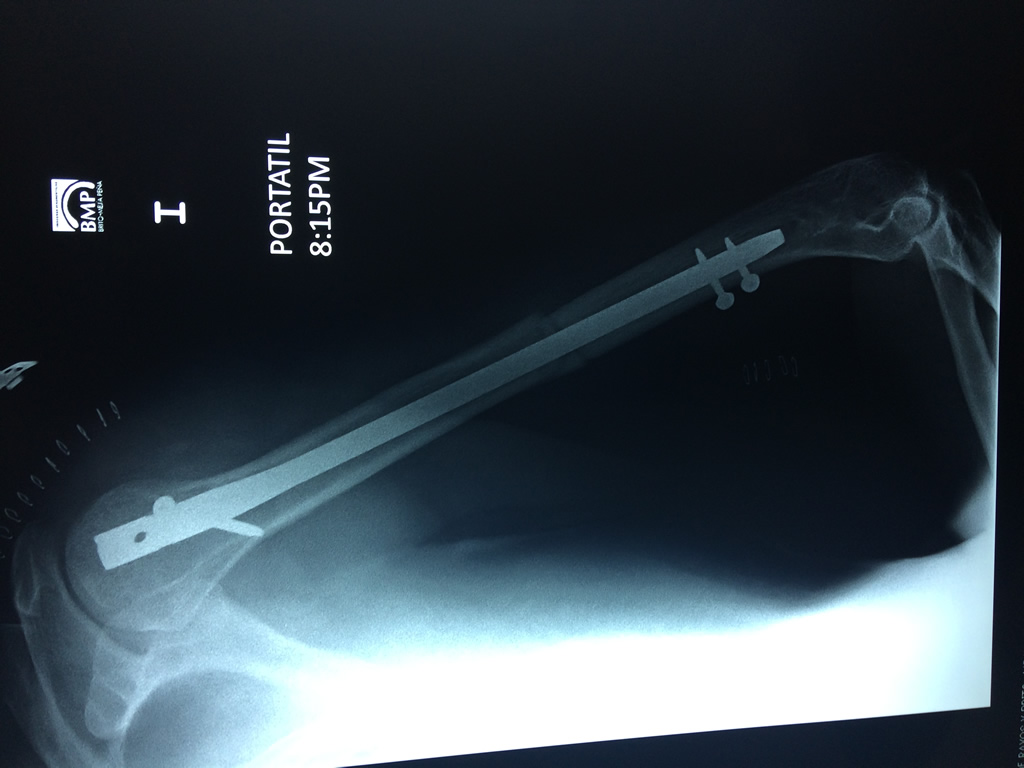

Calcaneo - Húmero

El Húmero (en latín, humerus) es el hueso más largo de las extremidades superiores en el ser humano. Forma parte del esqueleto apendicular superior y está ubicado en la región del brazo. ... El extremo proximal del húmero tiene la cabeza, cuellos quirúrgico y anatómico y tubérculos mayor y menor.